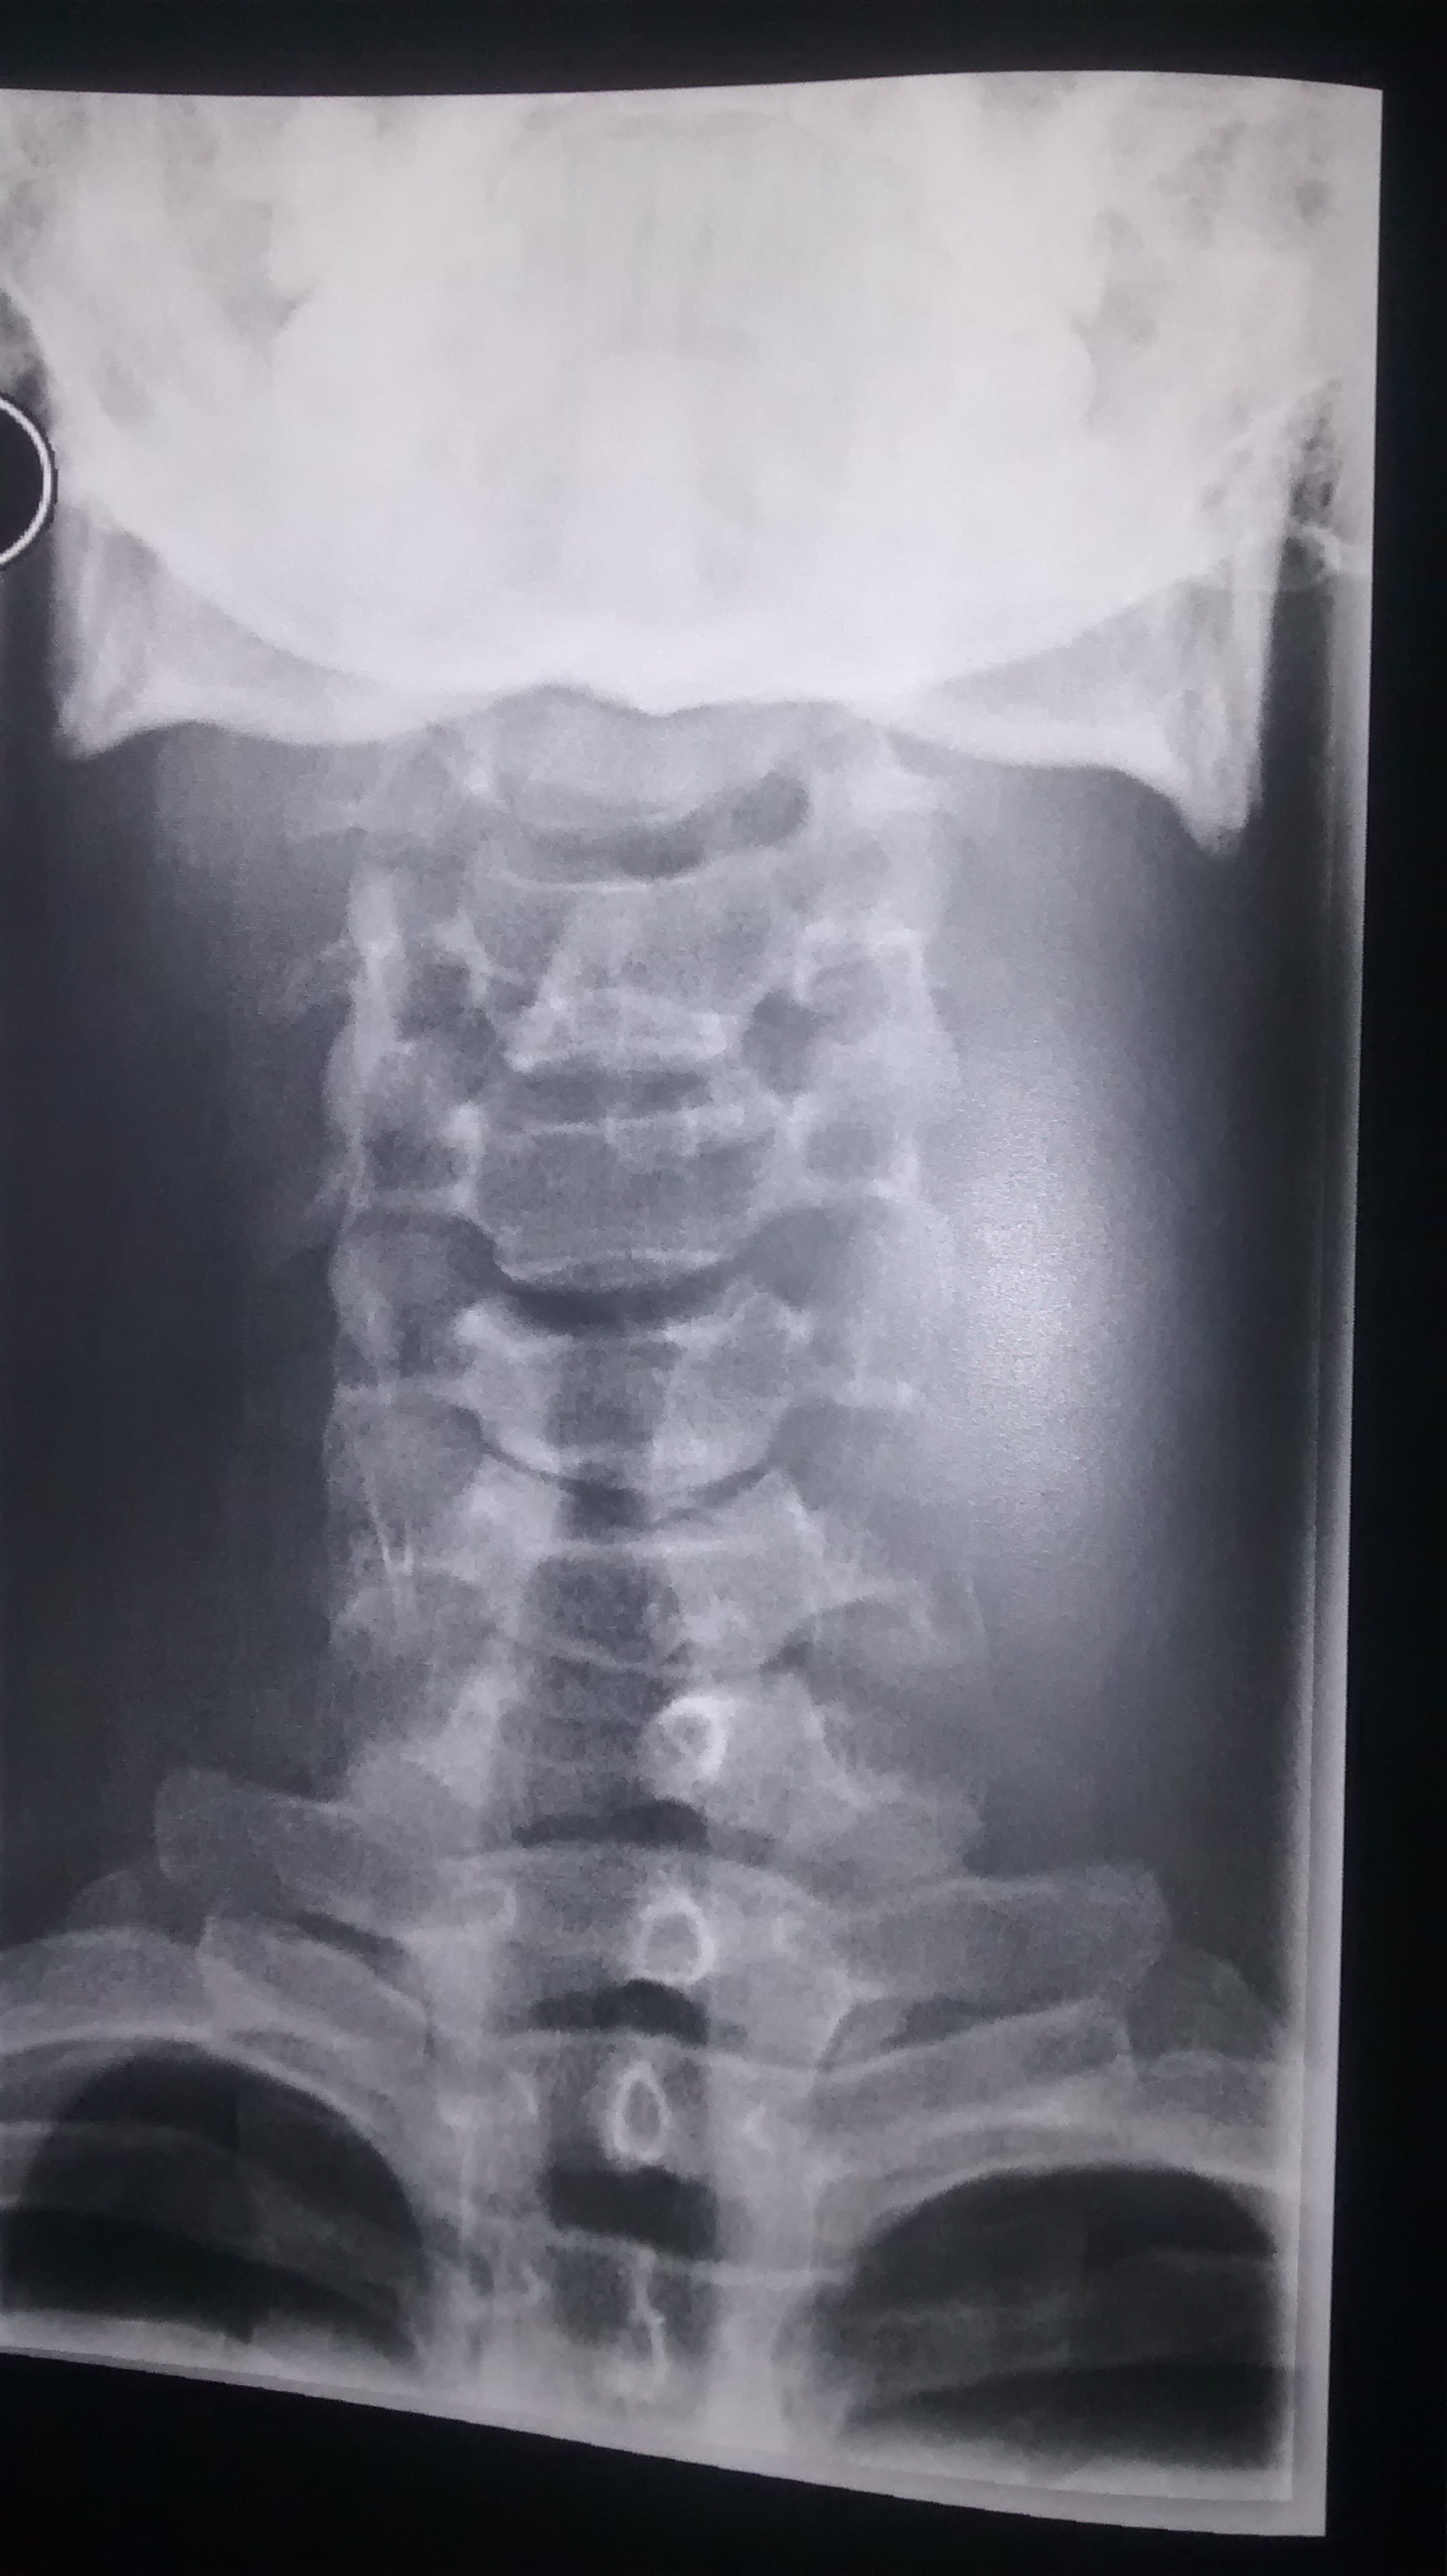

Weisse Flecken Auf Rontgenbild Von Halswirbelsaule Was Kann Das Sein Hals Rontgen